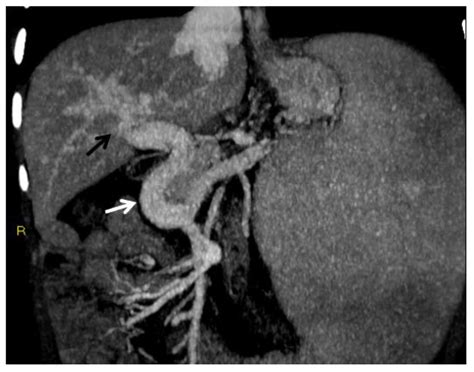

CT Angiography Provides detailed, cross-sectional images of the abdomen, clearly highlighting the thrombus and the extent of the blockage.

Magnetic Resonance Imaging (MRI) Excellent for detailed soft tissue visualization and helpful when CT contrast agents are not ideal.

Confirming a diagnosis of Portal Vein Thrombosis requires advanced imaging techniques to visualize the blood flow and the clot itself. Physicians will typically utilize non-invasive tools as the first line of defense.